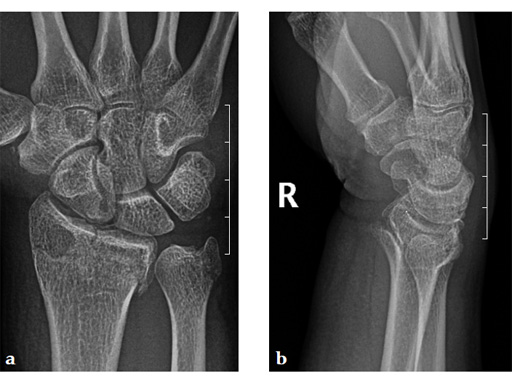

Case 1: A 62-year-old man fell on his outstretched left hand while playing tennis, sustaining an intraarticular fracture of the distal radius, Mller AO Classification 23-C3.2.

Case provided by Renato Fricker, Bruderholz, Switzerland